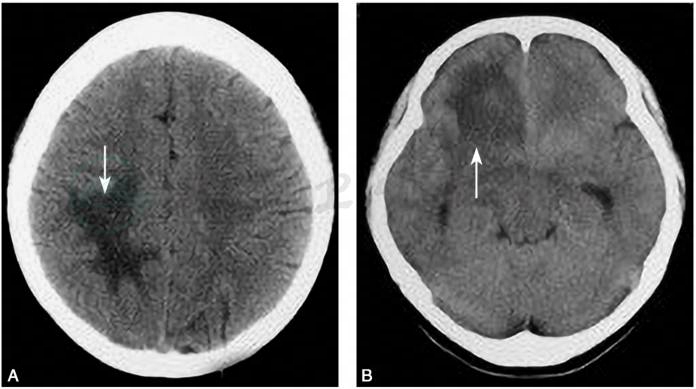

TIDD在CT平扫时绝大多数为边界较清楚的低密度影(图4A),个别可为等密度(图4B),CT强化多不显著。脑CT显示高密度病灶或周围有高密度环基本可除外TIDD诊断(Kim et al,2009)。

图4TIDD病灶密度

A.低密度病灶(箭头);B.等密度病灶(箭头)

引自:神经病学:全2册.第3版.ISBN:978-7-117-31406-0.主编: